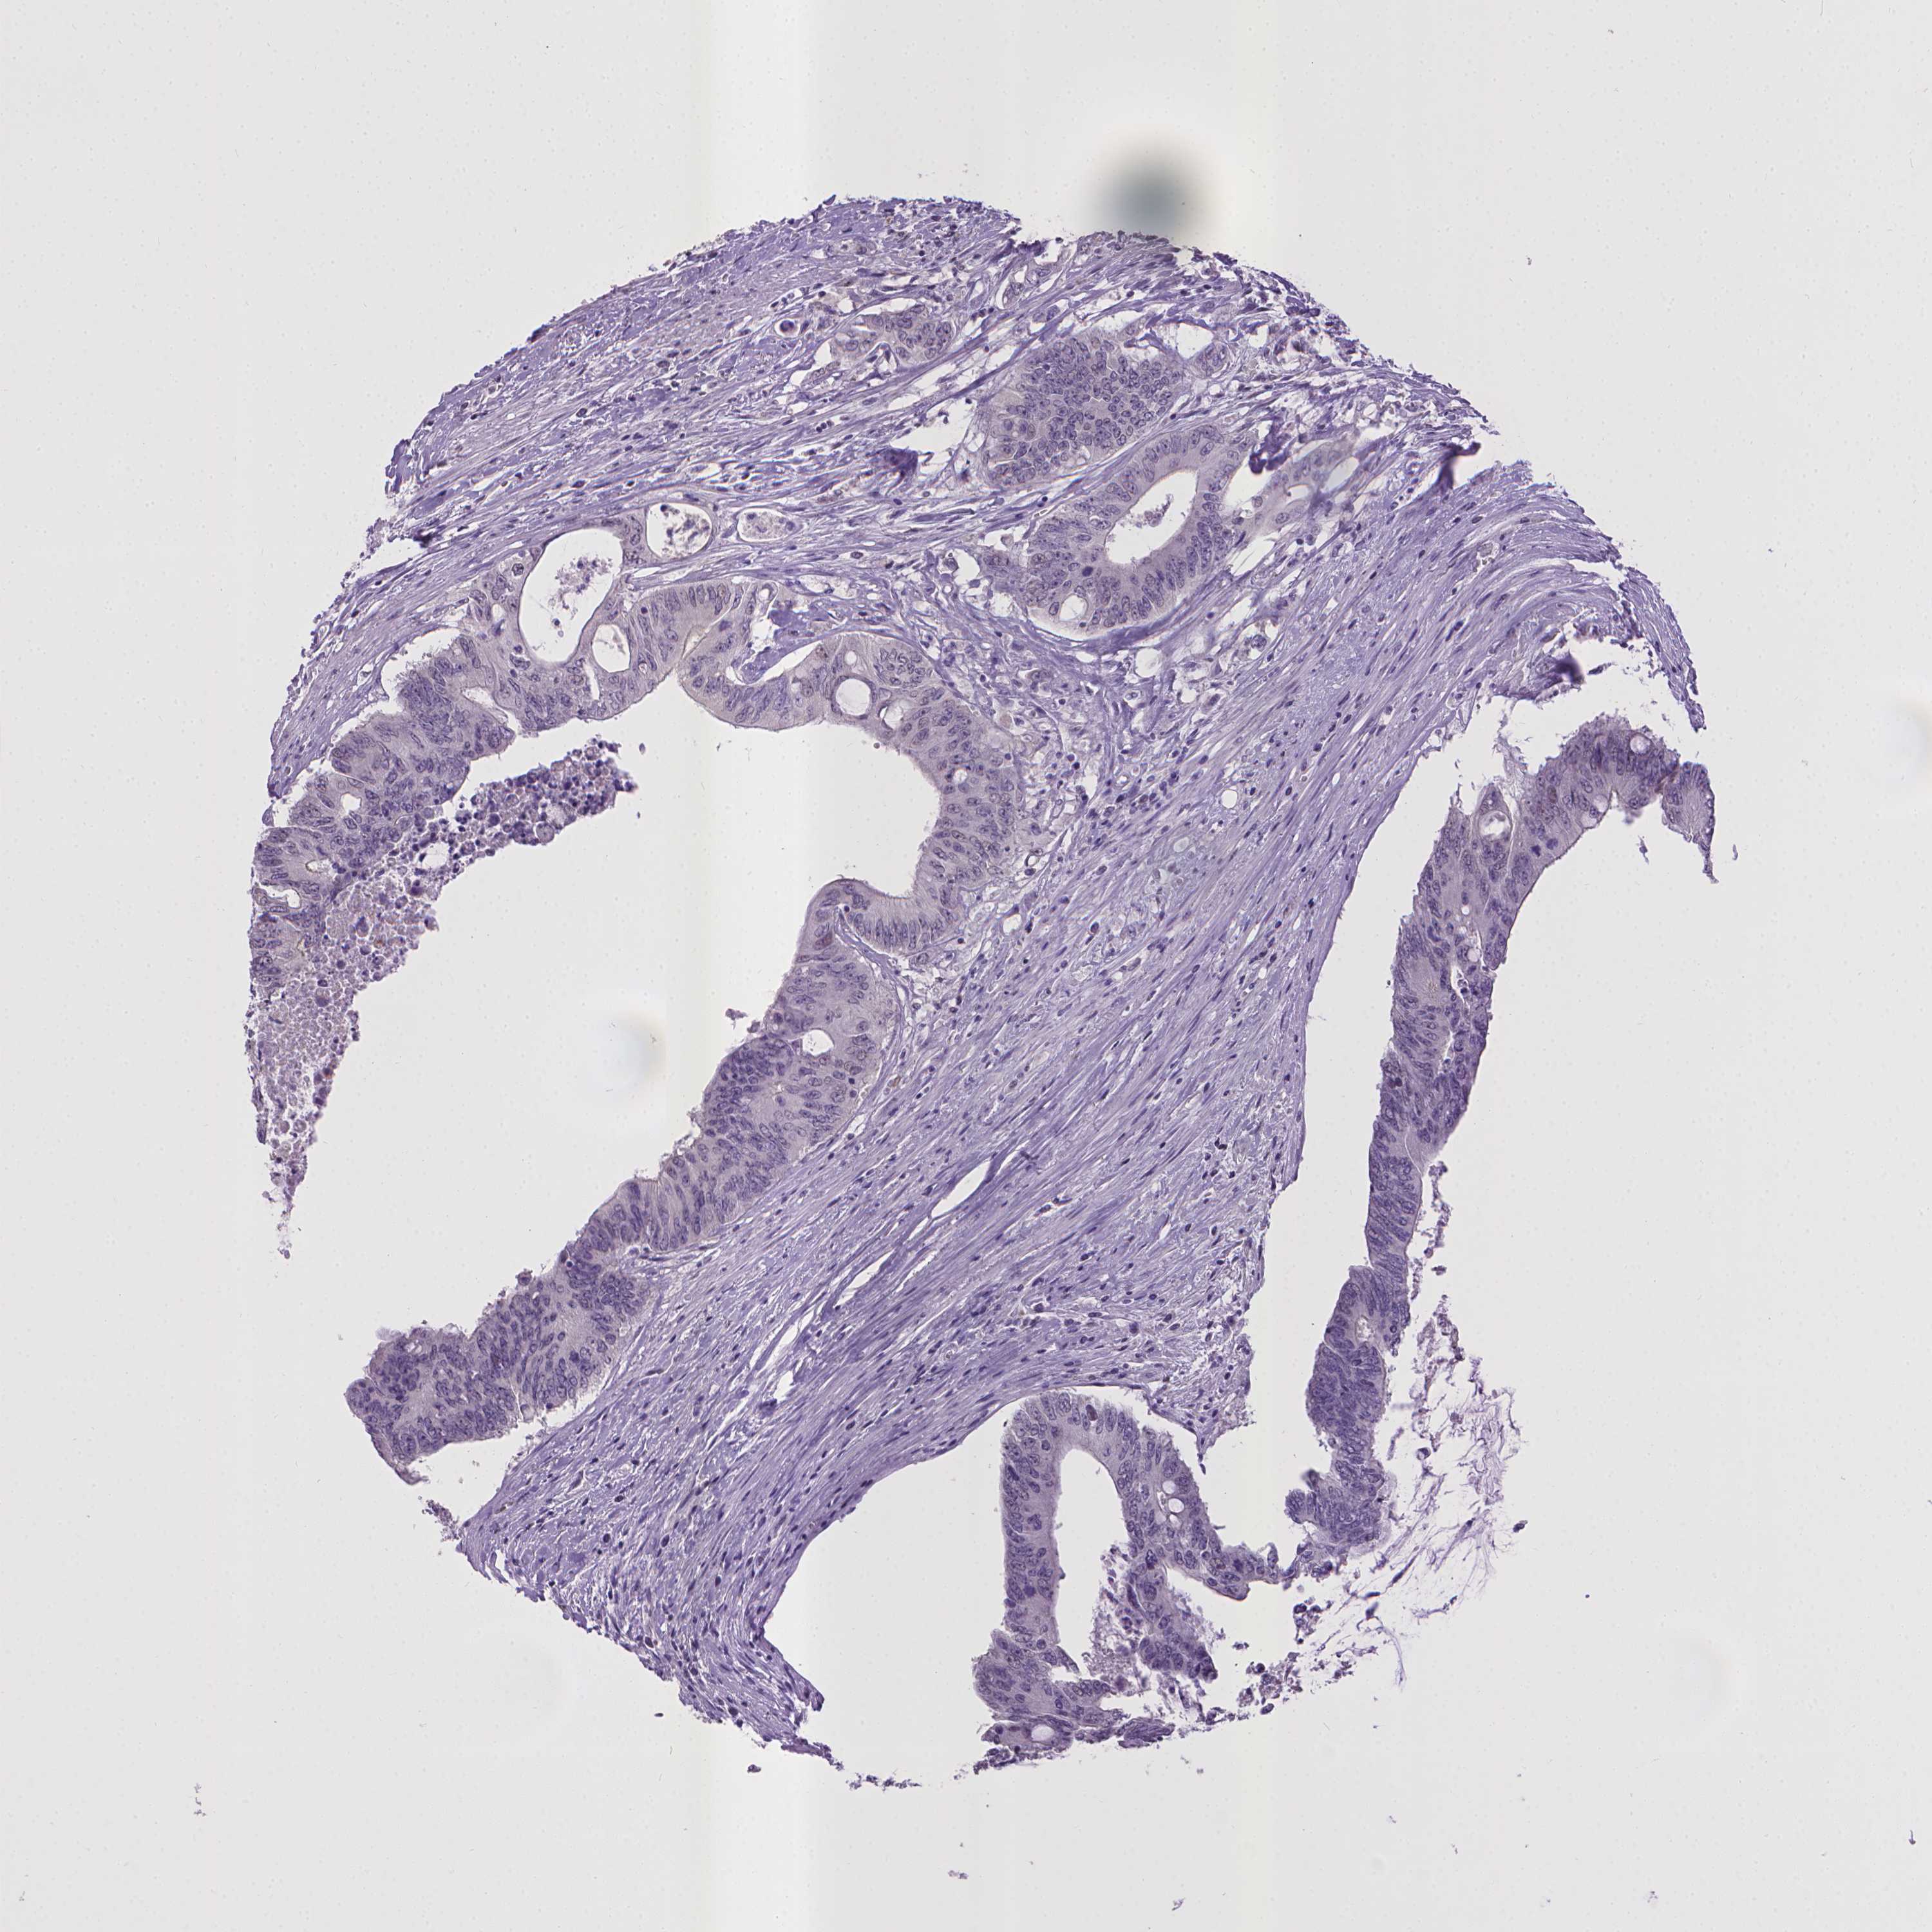

CANCER COLORECTAL CANCER Show tissue menu

Colorectal cancer

Human cancer